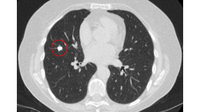

Computed tomography (CT) showing a posterior left upper lobe spiculated nodule, with ‘bronchus sign’ in a female non-smoker. Bronchoscopic forceps biopsy and brushing assisted by radial EBUS miniprobe localisation, confirmed a non-Hodgkin’s lymphoma

From the collection of Dr George Tsaknis, MD, PhD, FRCP(London), MRQA, MAcadMEd, PGCert; used with permission